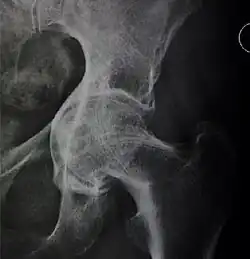

![Figure 5 (b). Coxa profunda.[3]](./_assets_/X-ray_of_coxa_profunda.jpg)

![Figure 5 (c). Protrusio acetabuli.[3]](./_assets_/X-ray_of_protrusio_acetabuli.jpg)